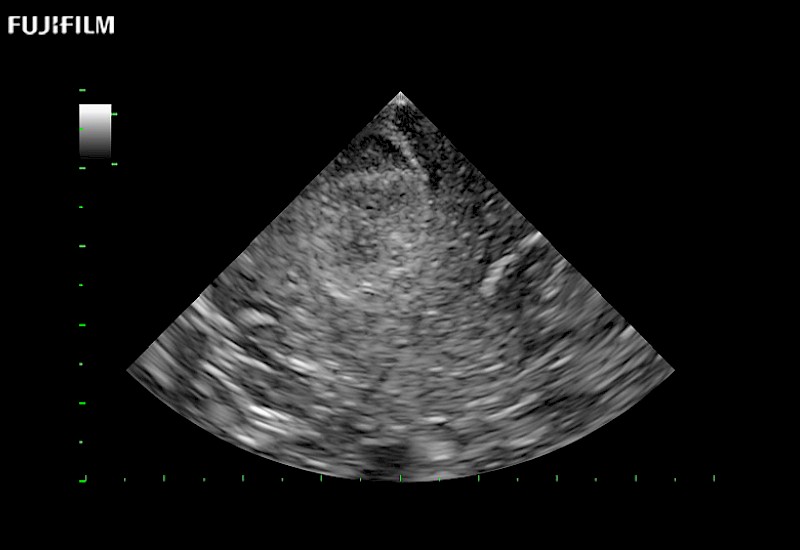

Tight curved (12mm) array transducer that is ideal for scanning during cranial guidance procedures.

Main Specifications:

Smaller footprint (20mm) curved array transducer that is ideal for scanning during cranial guidance procedures.